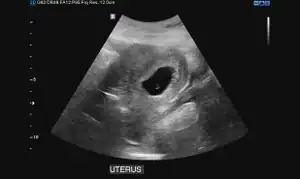

Obstetric ultrasonography may also be used to detect and diagnose pregnancy. It is very common to have a positive at home urine pregnancy test before an ultrasound. Both abdominal and vaginal ultrasound may be used, but vaginal ultrasound allows for earlier visualization of the pregnancy. With obstetric ultrasonography the gestational sac (intrauterine fluid collection) can be visualized at 4.5 to 5 weeks gestation, the yolk sac at 5 to 6 weeks gestation, and fetal pole at 5.5 to 6 weeks gestation. Ultrasound is used to diagnose multiple gestation.[3][19]

-

Ultrasound: early pregnancy -

Ultrasound: failed early pregnancy

Ultrasound is also a common tool for determining viability and location of a pregnancy. Serial ultrasound may be used to identify non-viable pregnancies, as pregnancies that do not grow in size or develop expected structural findings on repeated ultrasounds over a 1-2 week interval may be identified as abnormal.[34] Occasionally, a single ultrasound may be used to identify a pregnancy as non-viable; for example, an embryo that is greater than a certain size but that lacks a visible heart beat may be confidently determined to be not viable without the need for follow up ultrasound for confirmation.[34]